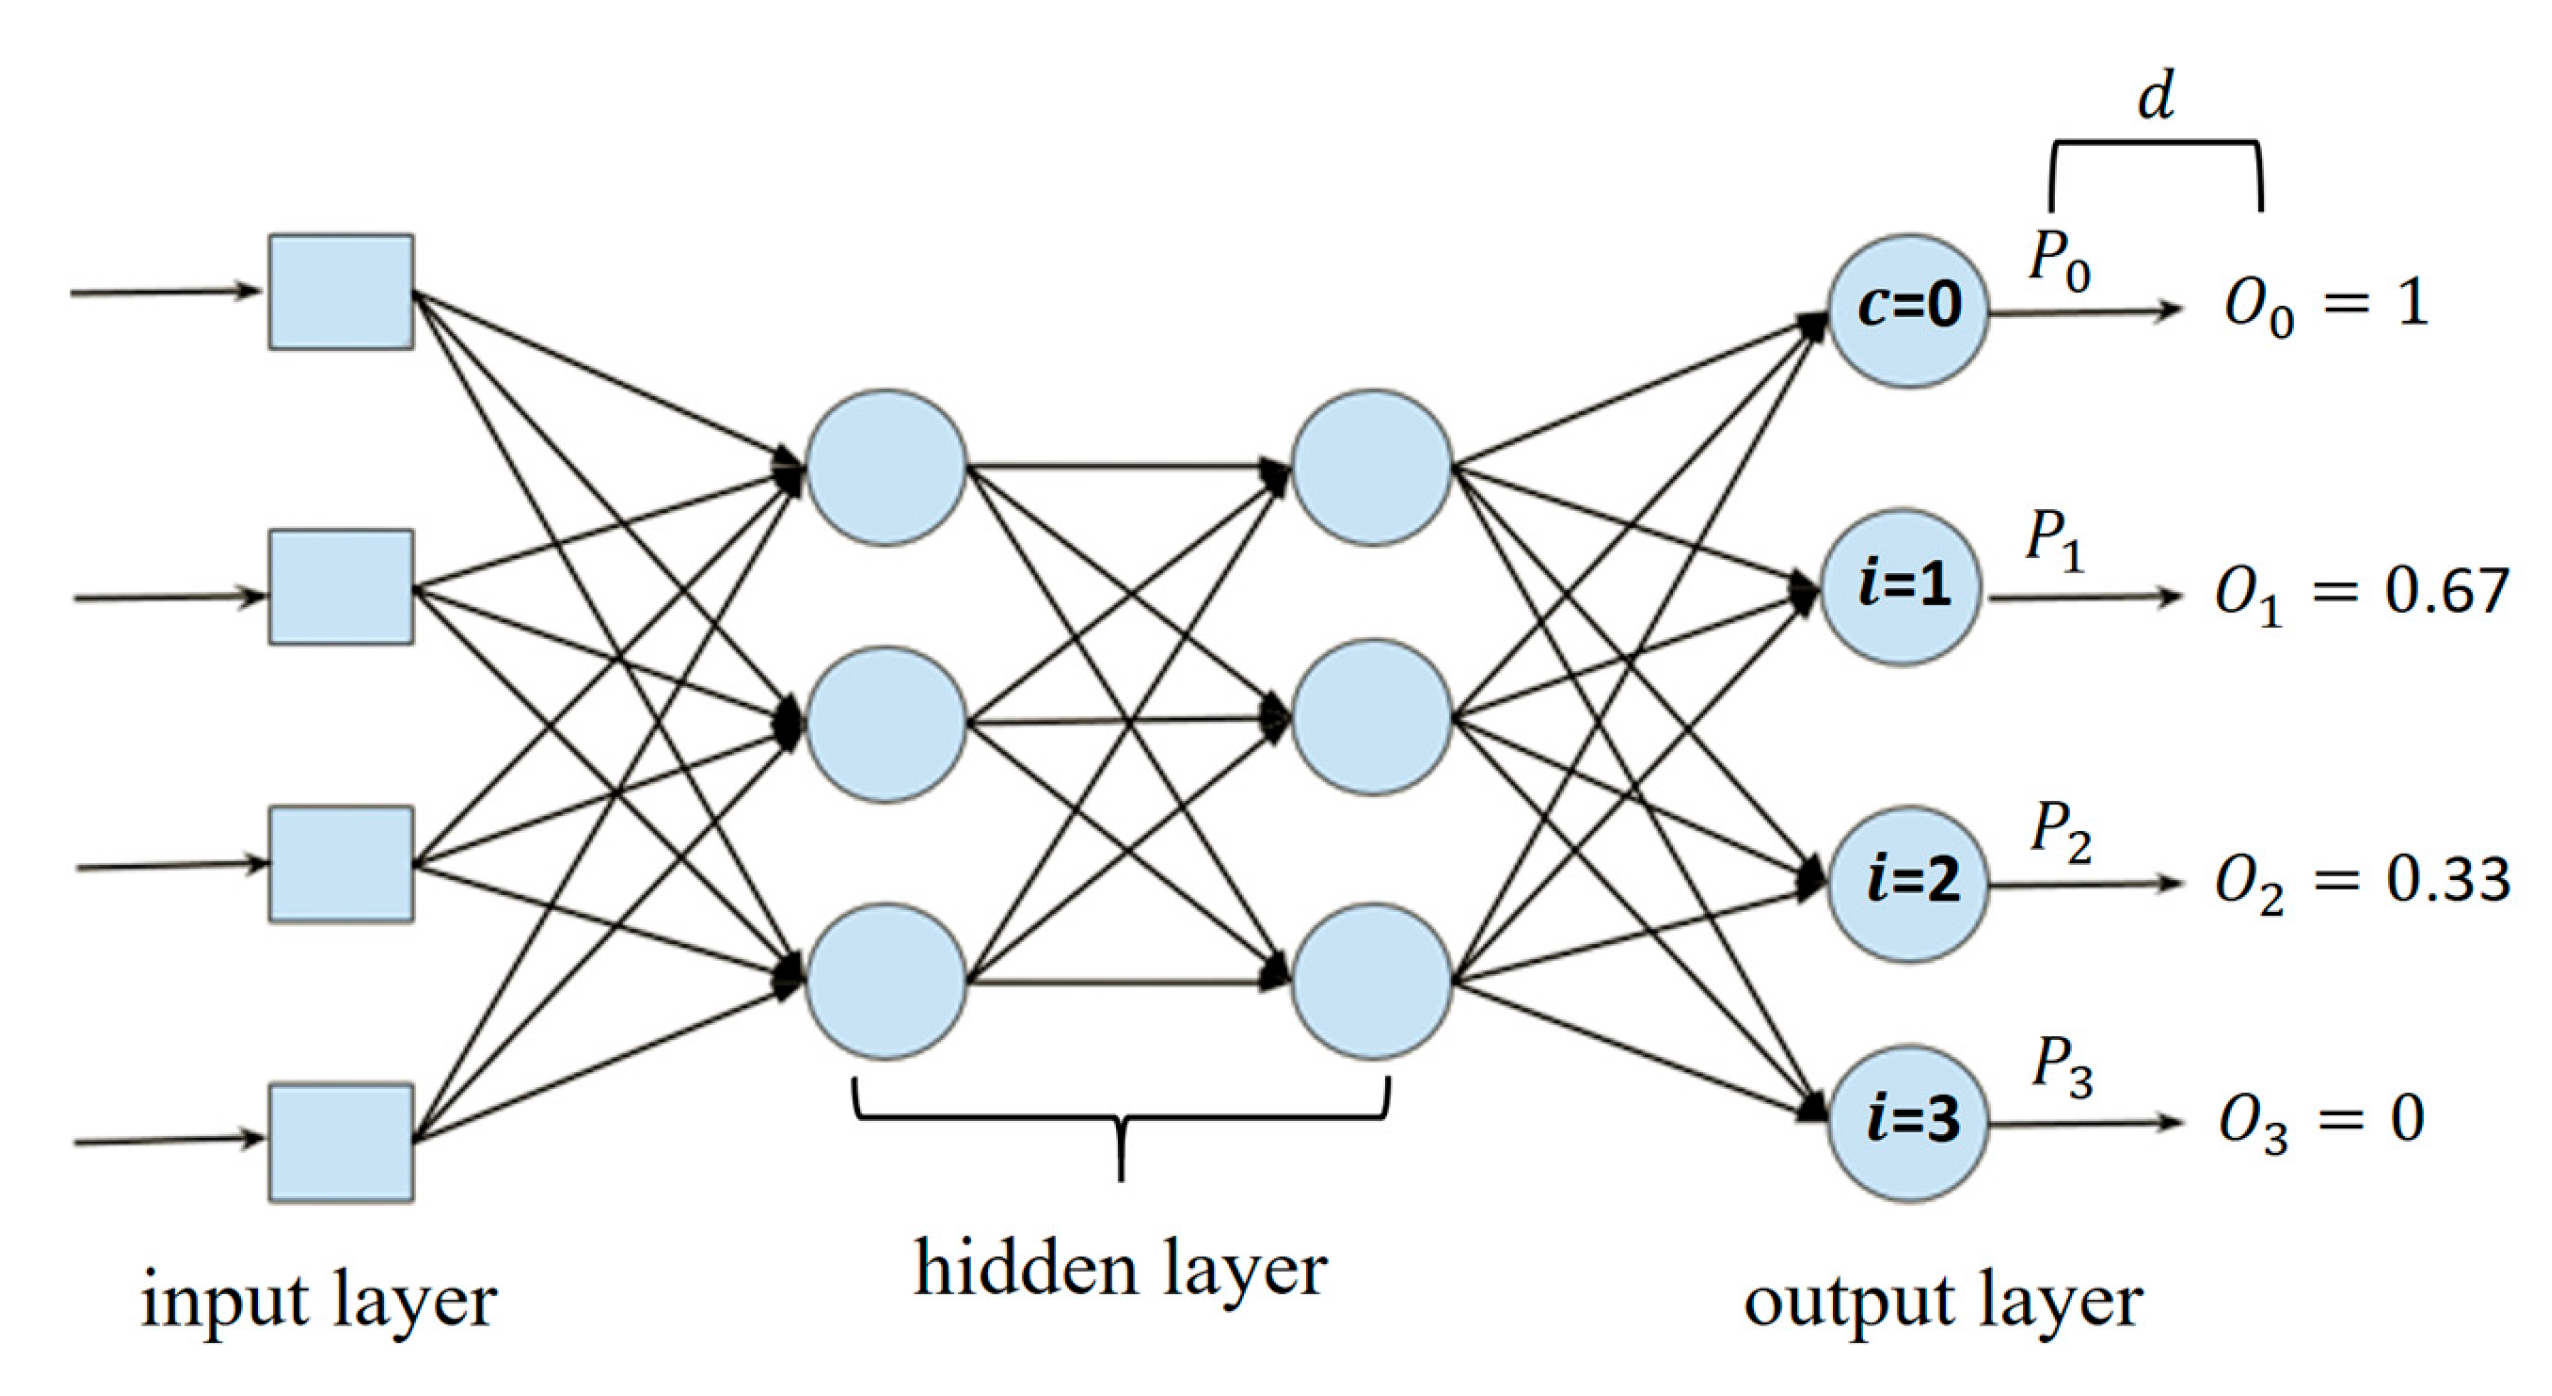

2.1. Ordinal Regression Based on Binary Classification

2.2. Addressing Inconsistencies in Predicted Probabilities Across Ordinal Levels

3.2. Ordinal Residual Dual Loss